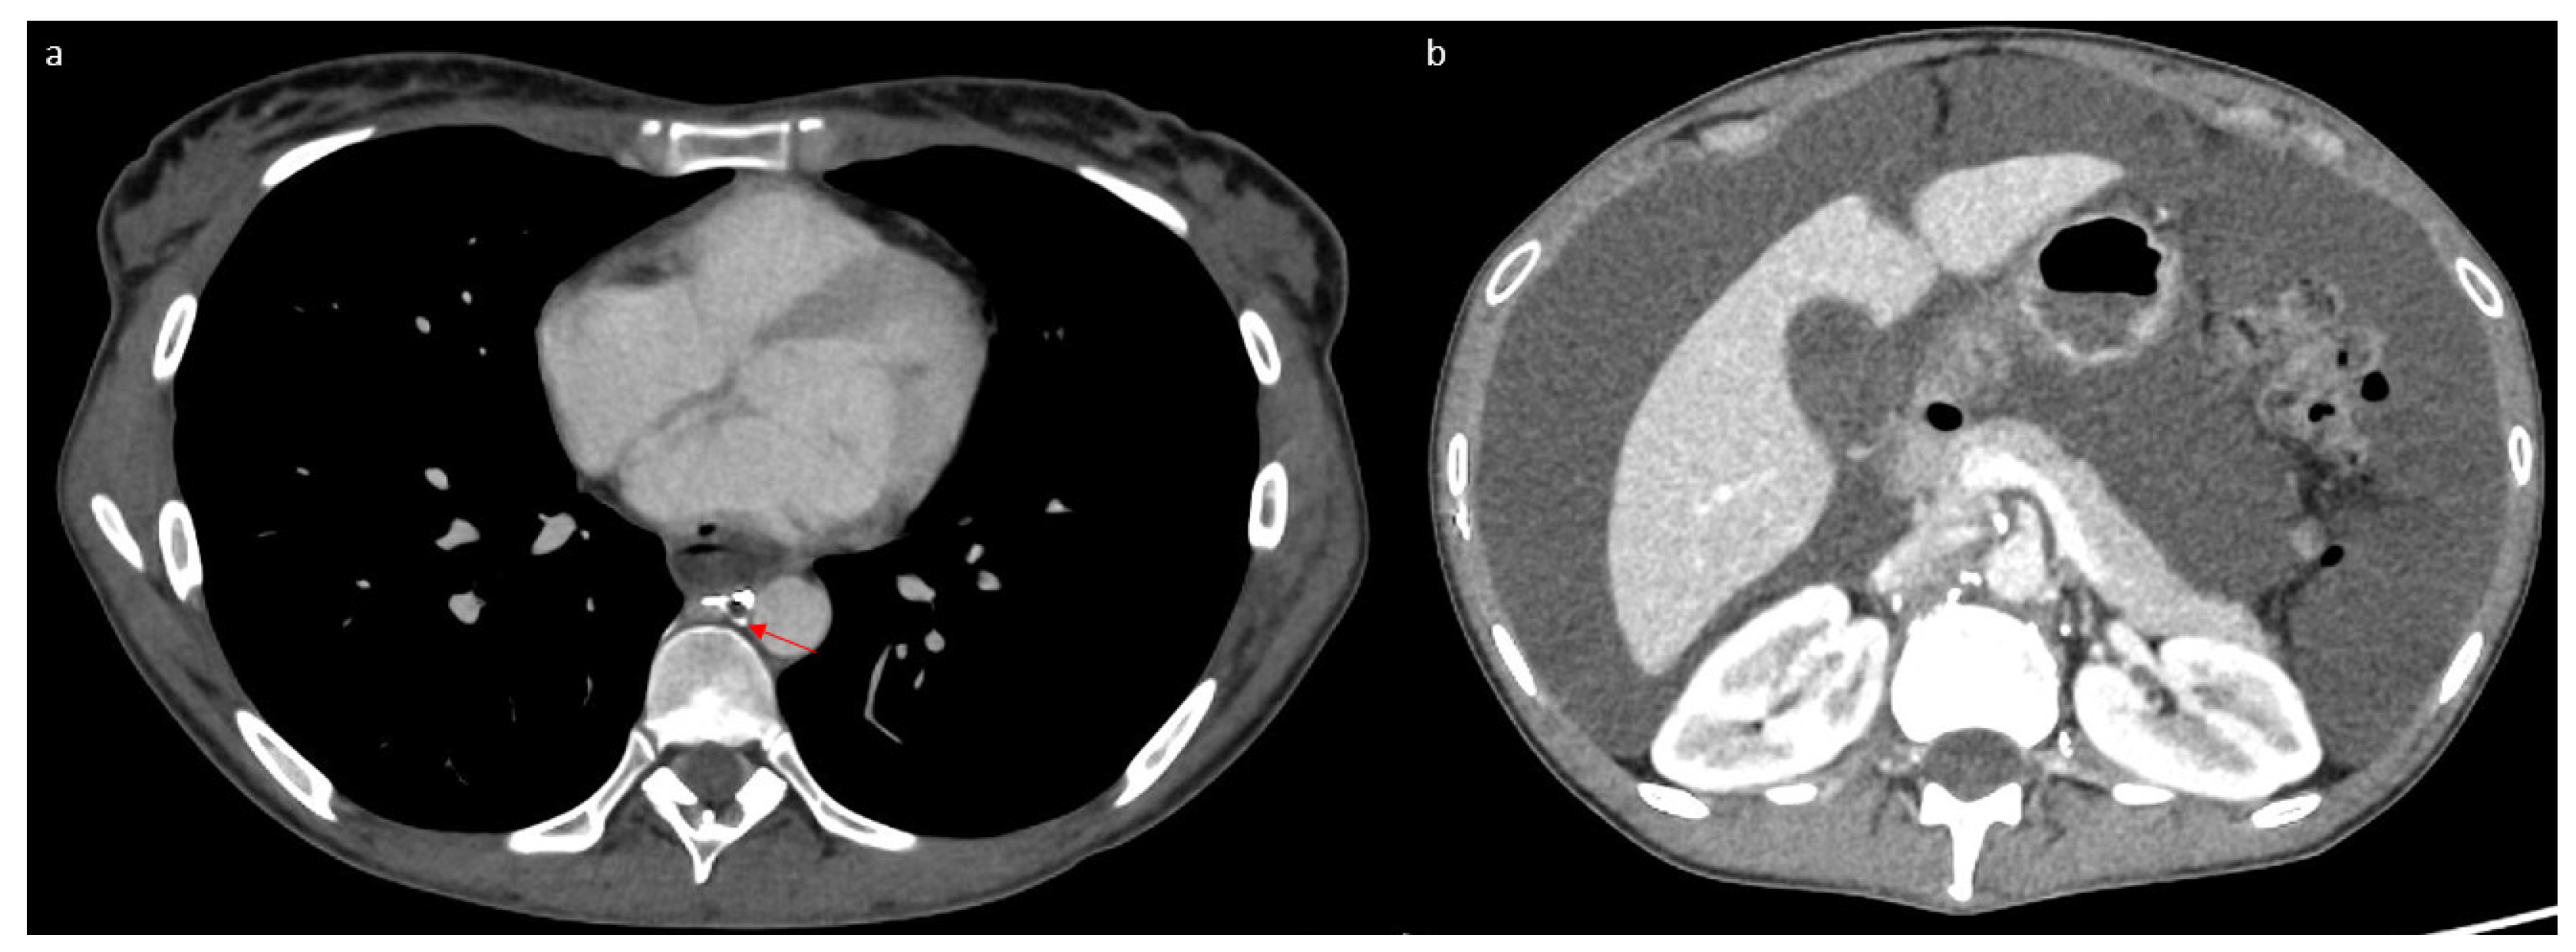

2. Case Report

3.1. Case Discussion and Physiopathological Hypothesis

3.2.3. Imaging